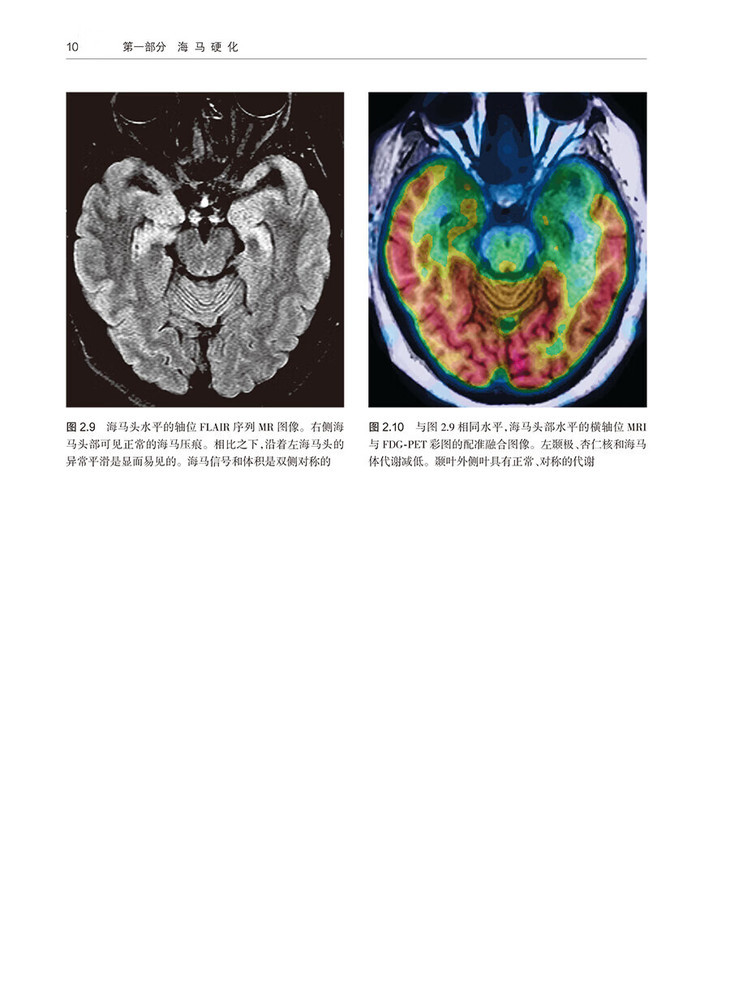

2 中度单侧海马硬化 /7